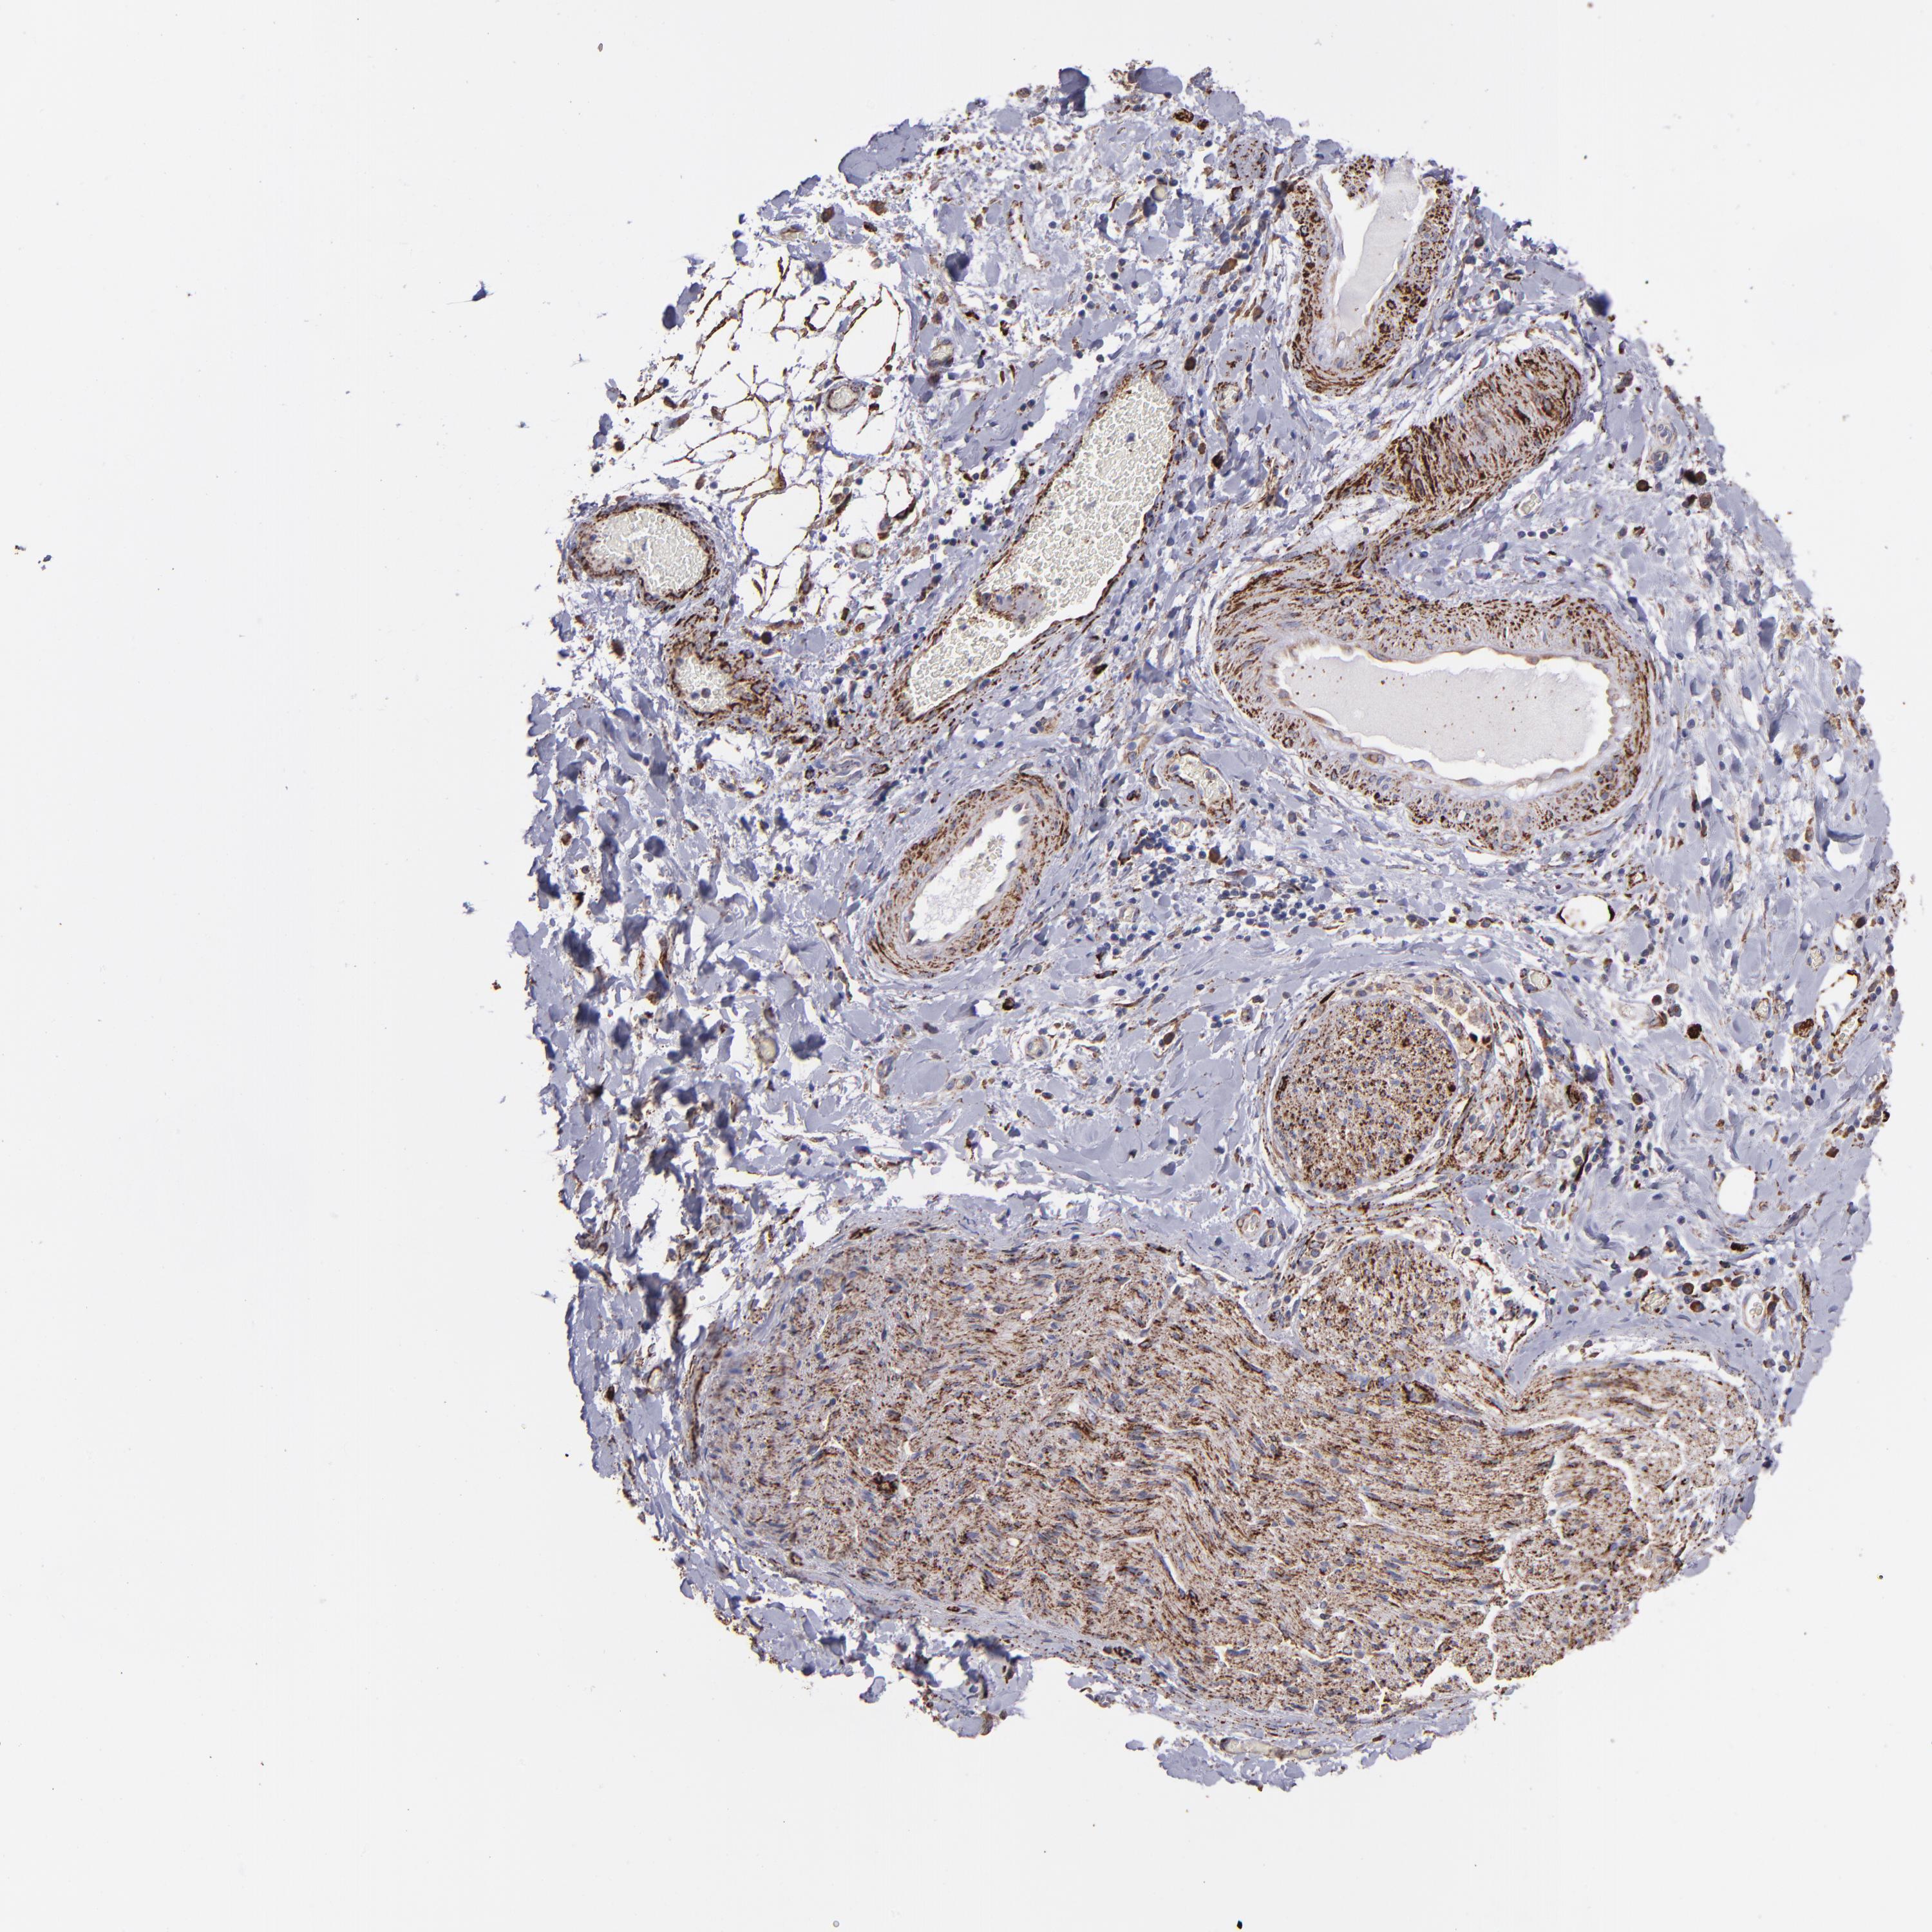

LIVER CANCER - Protein expressioni

A mouse-over function shows sample information and annotation data. Click on an image to view it in a full screen mode. Samples can be filtered based on level of antibody staining by selecting one or several of the following categories: high, medium, low and not detected. The assay and annotation is described here.

Note that samples used for immunohistochemistry by the Human Protein Atlas do not correspond to samples in the TCGA dataset.

Antibody stainingi

Antibody staining in the annotated cell types in the current human tissue is reported as not detected, low, medium, or high, based on conventional immunohistochemistry profiling in selected tissues. This score is based on the combination of the staining intensity and fraction of stained cells.

Each image is clickable and will lead to virtual microscopy that enables deeper exploration of all samples and also displays staining intensity scores, fraction scores and subcellular localization as well as patient and tissue information for each sample.

Antibody HPA002328

Antibody CAB037200

Staining

High

Medium

Low

Not detected

Intensity

Strong

Moderate

Weak

Negative

Quantity

>75%

75%-25%

<25%

None

Location

Nuclear

Cytoplasmic/membranous

Cytoplasmic/membranous,nuclear

Carcinoma, Hepatocellular, NOS

Cholangiocarcinoma